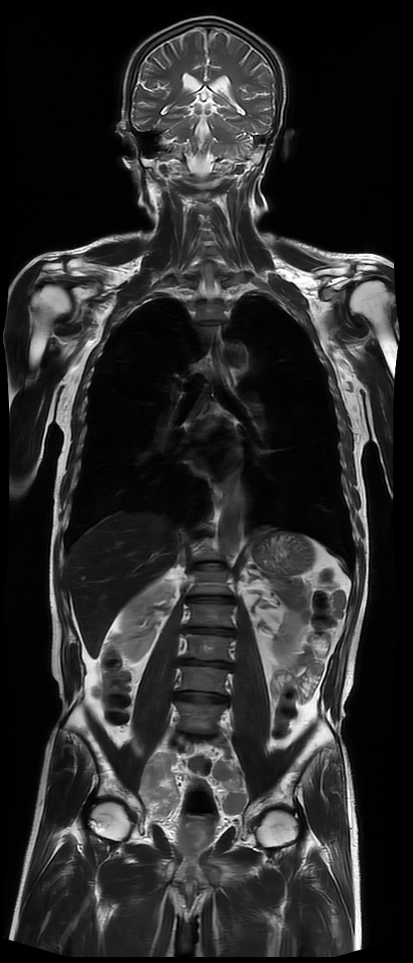

此次引进的联影3.0T光梭磁共振成像系统,是我县第一台3.0T高端磁共振设备,也是国际最先进的医疗检查设备之一,达到了北京、上海等大型三甲医院的主流装备水平。与1.5T磁共振比较,3.0T磁共振凭借业界领先的超高性能梯度系统、搭载全新光梭技术平台,实现超高速及超高清的磁共振检查,开启磁共振精致极速成像时代。

该设备还搭载了丰富全面的高级应用及AI应用,如全身类PET、肝脏脂肪定量分析、3D ASL脑灌注分析、高清小视野弥散、全脊柱自动拼接、颈动脉斑块分析等,为临床、科研的前沿探索与研究提供了有力工具。

磁共振检查没有任何电离辐射,理论上对人体没有危害,是临床上最为安全的影像检查和诊断方法,分辨率较高,可对神经系统、乳腺、腹部、盆腔、脊柱、全身各关节等部位开展形态学及功能学成像,提供高清、精准的影像诊断信息。尤其是在血管壁显示、关节韧带等体素扫描、腹部动脉多期强化扫描等方面具有比1.5T磁共振不可比拟的优势。